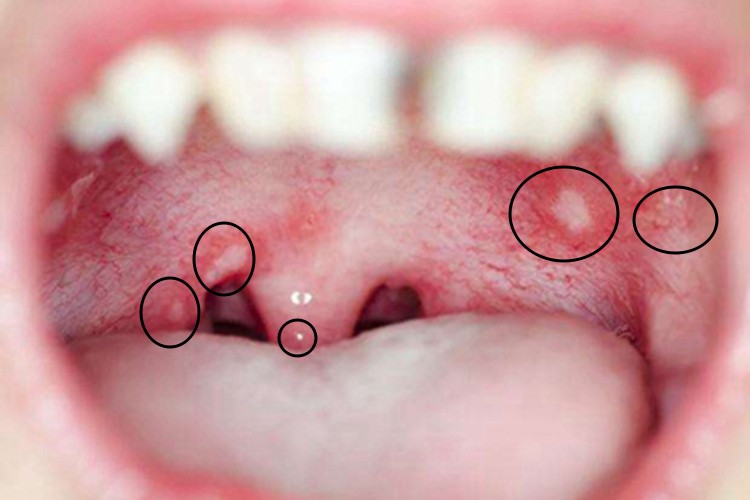

疱疹性口炎多急性起病,黏膜可发生成簇的小水疱和散在的单个水疱,周围绕以红晕,很快破溃,形成浅表溃疡,上覆黄白色纤维性渗出物,溃疡边界清楚。由于疼痛剧烈,常伴有拒食、流涎、烦躁等。